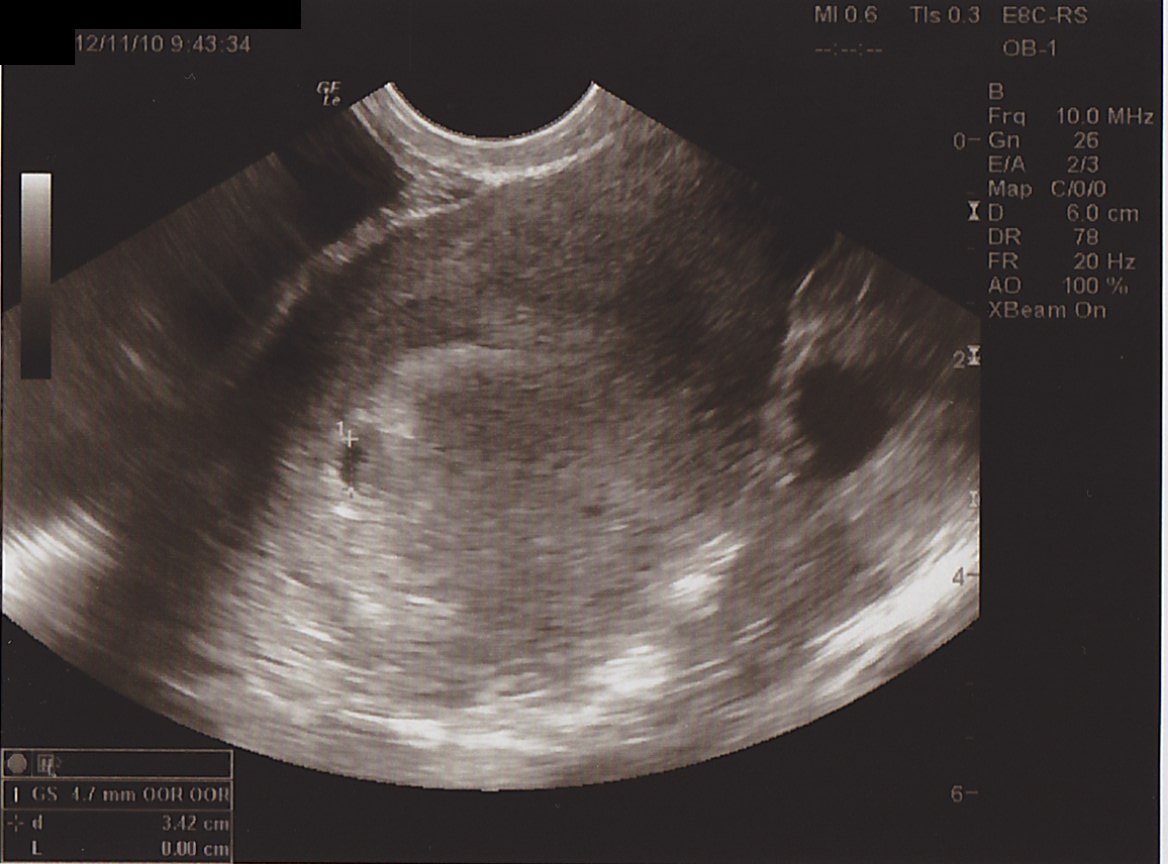

どきどき の 超音波検査。

そこには…

ちいさな ふくろ = 「胎嚢 ( たいのう )」 がありました。

▲ 中心より ちょっと左側にあるのが、 モンちゃん袋。

このときはまだ、 だれもいないけど、

ここは いずれ、

羊水 と あかちゃん が はいる

たいせつな場所、 なんだって。。